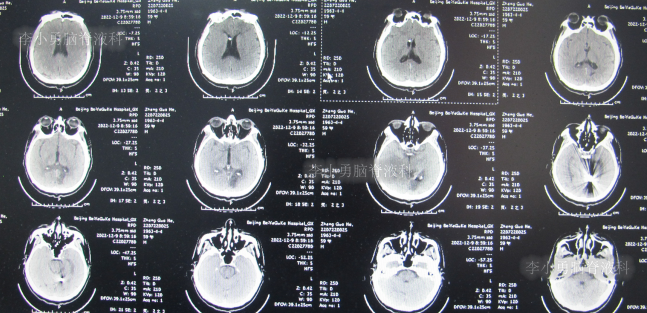

2022年9月13日(住院治疗53天),常规查头颅CT示脑室引流术状态(图-22)。

图-22:2022年9月13日头颅CT

2022年10月11日(住院治疗80天),进行了脑室腹腔分流术。脑室腹腔分流术次日查头颅CT和身体均无异常(图-23)。

图-23:2022年10月12日头颅CT

2022年12月9日(李小勇脑脊液科治疗4月余)出院,出院时:身体一切正常(图-24),头颅CT未见异常(图-25)。

图-25:出院时头颅CT